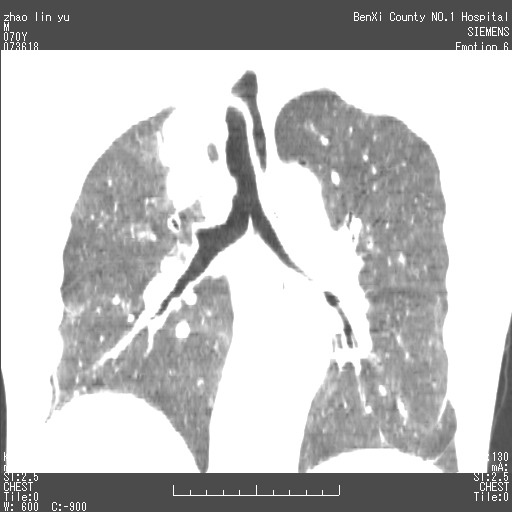

以下是引用王靖旗在2007-7-10 17:12:00的发言:[br] 男、70、咳嗽两个月,半年前换瓣手术,胸片未见异常,于昨天行x片发现右肺上野大片影,行ct扫描,这里是减薄图像,余肺正常。明天晚上会有增强扫描片,到时我会上传。[br][br] 冠状位请大家细看,应该是有意义的,[br][br] 请大家先看平扫发表意见。[br][br]

[br]冠状面[br]